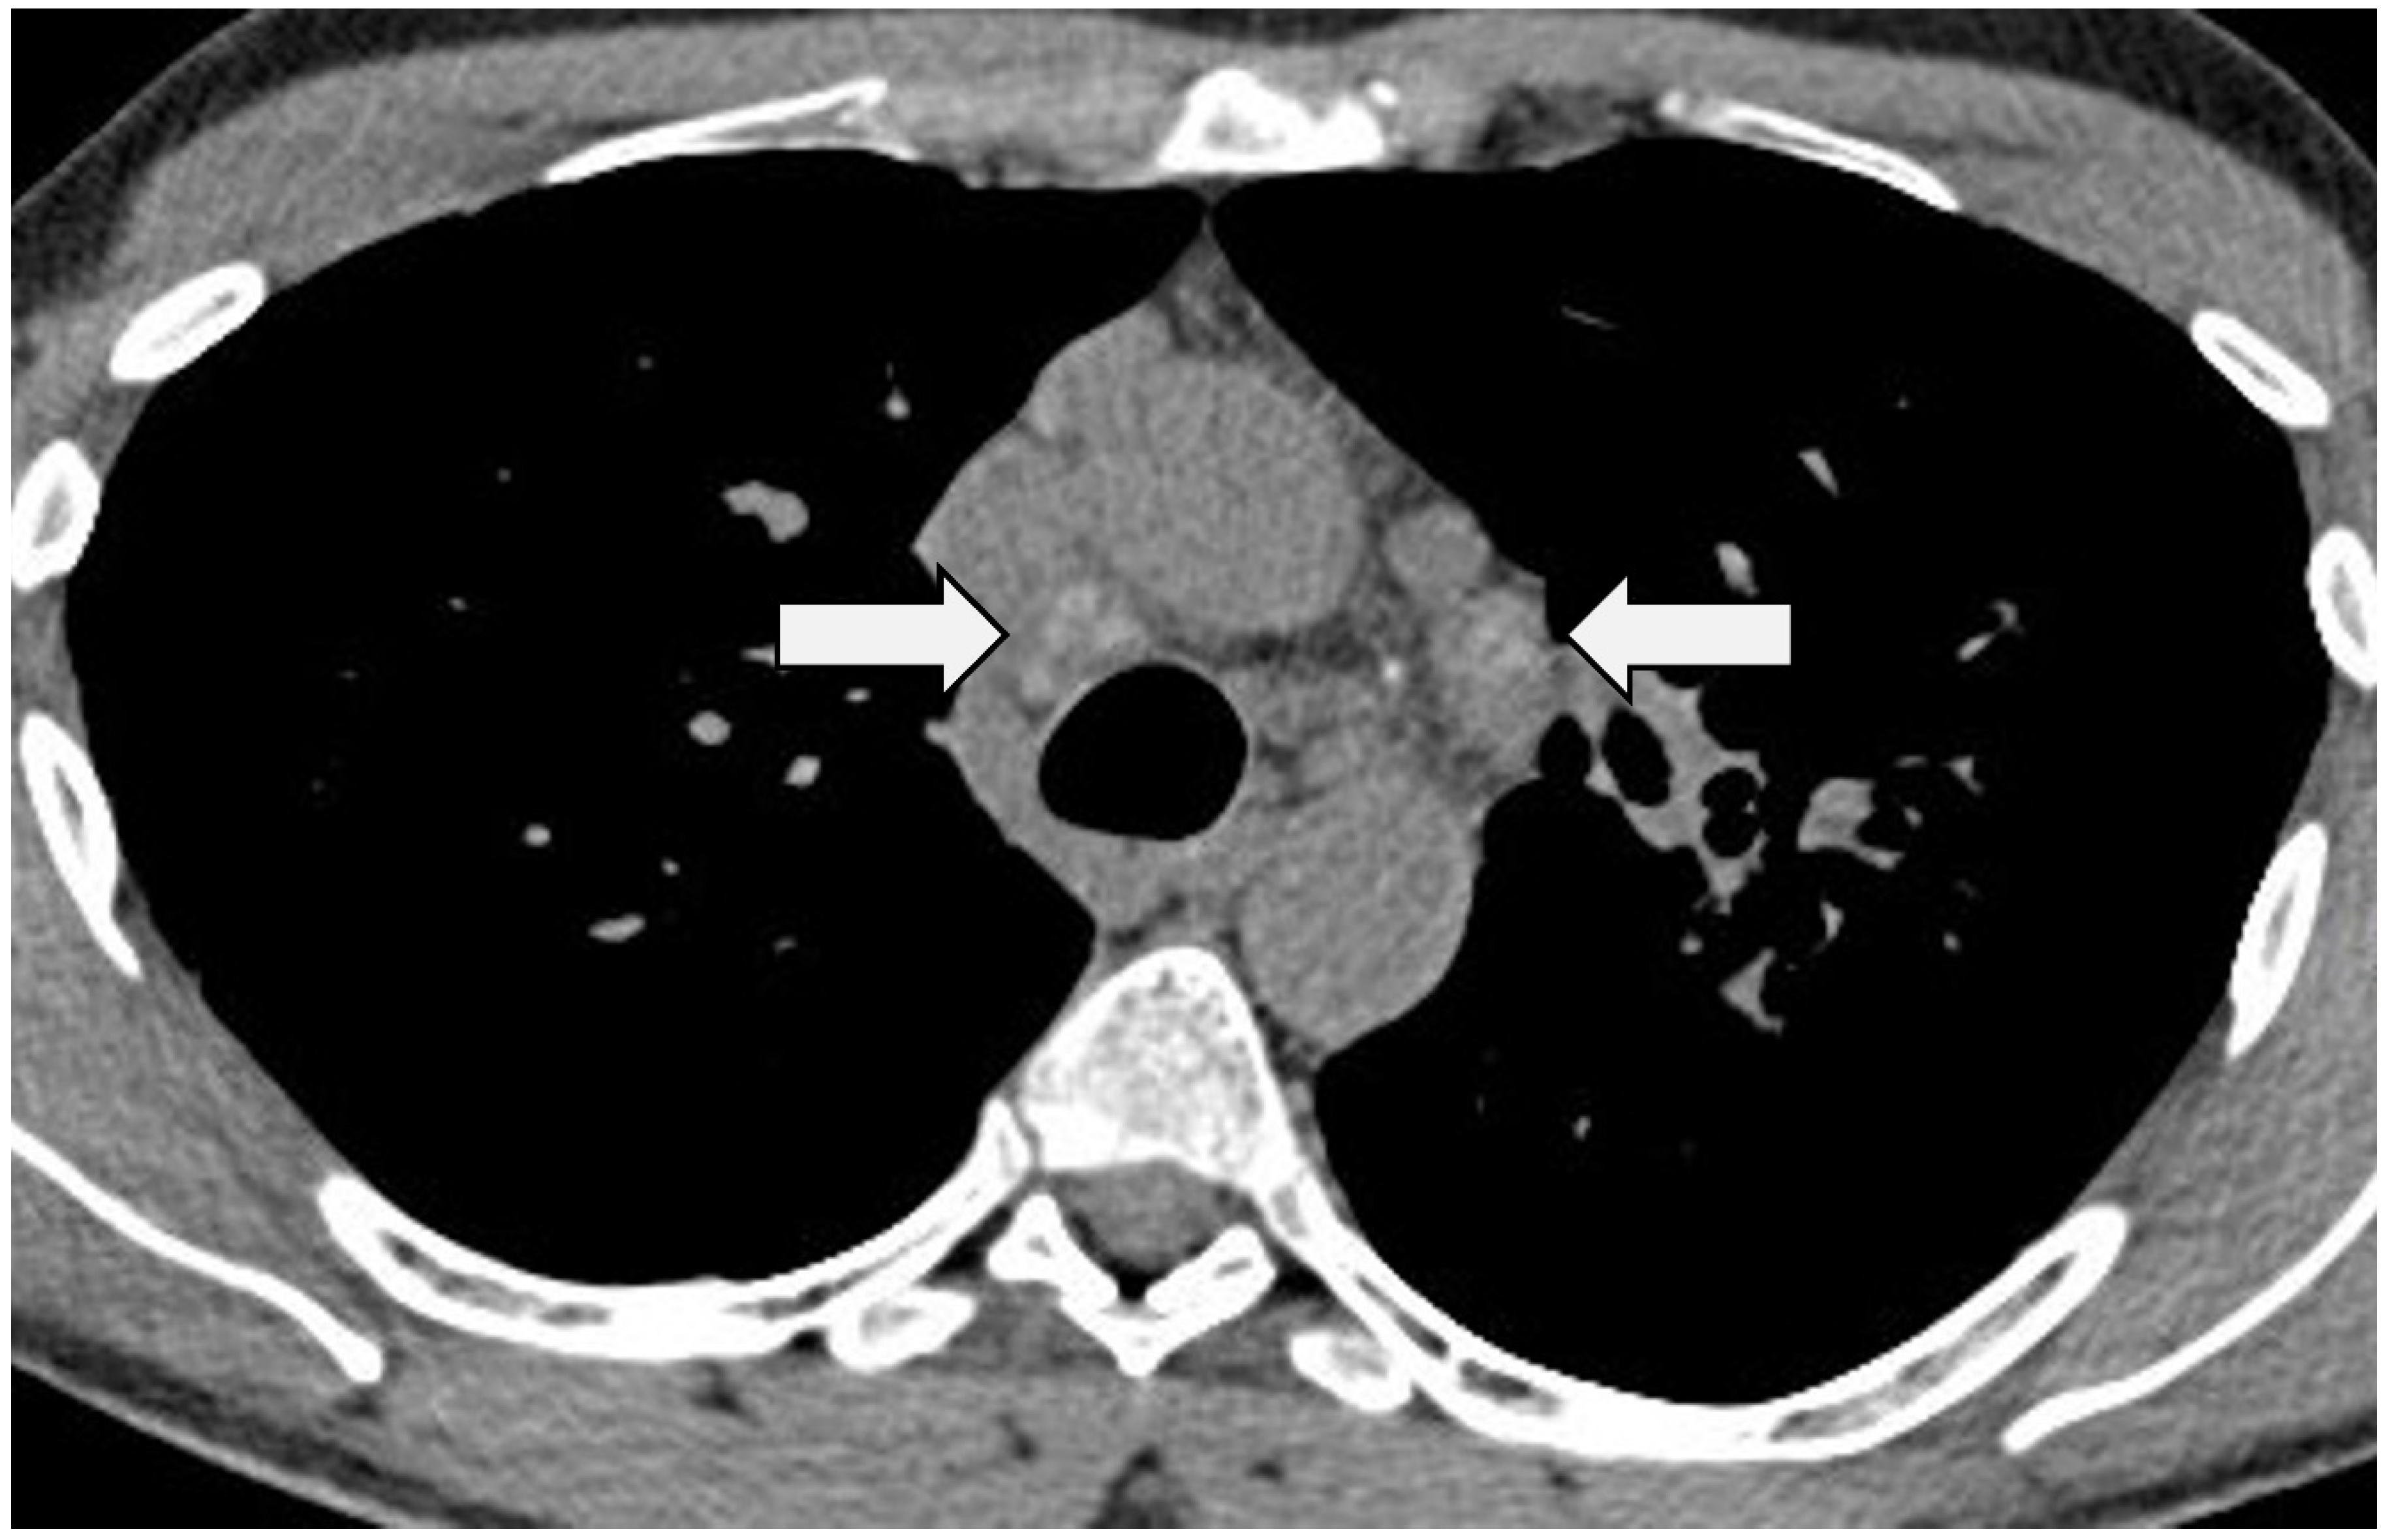

Figure 1.

Axial CT in a patient with sarcoidosis. Images at a level below the aortic arch demonstrating classical ‘icing sugar’ calcification in mediastinal lymph nodes (arrows).